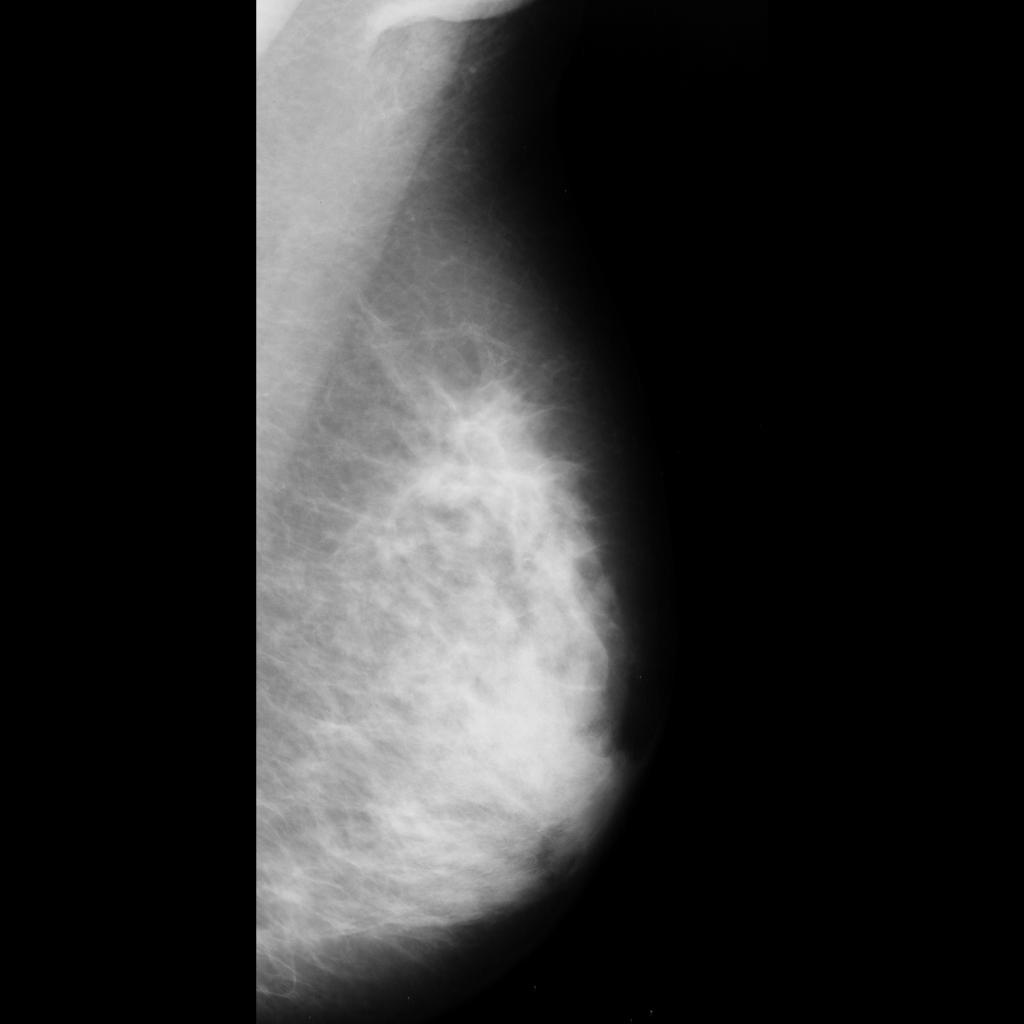

malignant